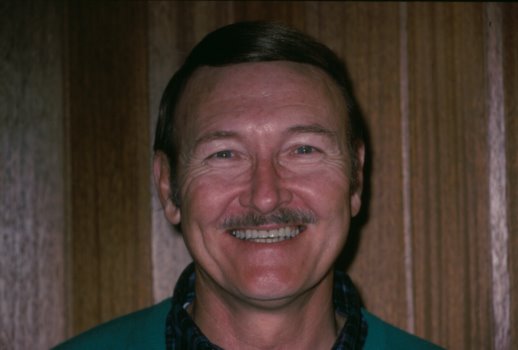

This patient is congenitally

missing his lateral incisors, that is, he was born without the two teeth

that are normally located next to the front teeth. Through the use of

orthodontic appliances, we brought the canines (eye teeth) back and

closed the gap between the front teeth to make enough room for

artificial teeth. Then, bridgework was prepared and cemented in

permanently. |